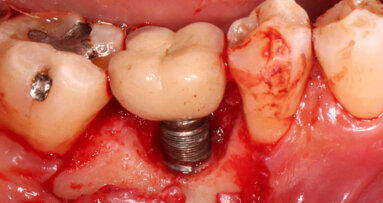

GOTEMBURGO, Suécia: Implantes de dentes individuais demonstraram altas taxas de sucesso em períodos de observação de cinco a dez anos. No entanto, o monitoramento de longo prazo continua essencial. Pesquisadores da Universidade de Gotemburgo conduziram recentemente o mais longo estudo de acompanhamento até agora sobre sobrevivência de implantes e taxas de complicação, avaliando implantes individuais colocados de 38 a 40 anos atrás. Suas descobertas confirmaram que os implantes permaneceram totalmente funcionais, mas que as coroas suportadas por implantes exibiram vidas úteis comparativamente mais curtas. O estudo oferece insights valiosos sobre potenciais complicações de longo prazo e reforça a confiança na longevidade dos tratamentos com implantes de dentes individuais.

O estudo incluiu 13 indivíduos que receberam 18 implantes únicos colocados usando um protocolo de dois estágios com carga tardia, e nenhum recebeu enxertos ósseos. Os implantes foram desenvolvidos com base em pesquisas conduzidas na Universidade de Gotemburgo sob a liderança do falecido Prof. Per-Ingvar Brånemark — um distinto médico e pesquisador sueco amplamente reconhecido como o pai da implantodontia moderna e o pioneiro da osseointegração.

O autor principal Sargon Barkarmo, um prosthodontista e professor sênior da universidade, expressou entusiasmo em relação à eficácia a longo prazo dos implantes, que mostraram uma impressionante taxa de sobrevivência cumulativa de 95,6%. Ele comentou em um comunicado à imprensa da universidade: “Embora o estudo tenha incluído um pequeno número de pacientes, os resultados mostram que os implantes permanecem no lugar e que a perda óssea ao redor deles permanece praticamente inalterada após 40 anos. Isso confirma que a fundação estabelecida por Brånemark ainda se mantém.”

Embora a mucosite peri-implantar fosse comum entre os participantes do estudo, nenhuma peri-implantite foi diagnosticada. No entanto, vários implantes exibiram profundidades de sondagem ≥ 6 mm, indicando a necessidade de monitoramento clínico contínuo. Placa foi observada em todos os dentes e implantes durante a visita de acompanhamento, e o índice médio de placa foi de 16,9% ± 11,6%. Os níveis ósseos ao redor de todos os implantes permaneceram notavelmente estáveis durante o período do estudo, e muitos até mostraram leve ganho ósseo.

Em contraste com a alta sobrevivência do implante, as coroas suportadas por implantes tiveram uma vida útil notavelmente mais curta. Apenas 60,9% das coroas originais permaneceram no lugar. Das 18 coroas, seis foram retidas por cimento. O autor sênior Dr. Jan Kowar, um protesista e professor sênior da universidade, explicou que as preocupações estéticas, em vez de falhas técnicas, foram a principal razão para as substituições de coroas. Ele observou que o desenvolvimento de materiais inovadores para coroas poderia avançar significativamente os resultados de longo prazo para tratamentos de implantes.

Apesar do tamanho relativamente pequeno da amostra, o estudo destaca o excelente sucesso a longo prazo dos sistemas de implantes de dentes individuais, ao mesmo tempo em que reconhece a crescente probabilidade de substituições de coroas por períodos prolongados. Os autores enfatizaram que estudos de acompanhamento mais longos são cruciais para melhor compreensão da longevidade do implante e potenciais complicações, particularmente porque muitos dos pacientes que recebem implantes individuais são jovens e, portanto, espera-se que mantenham seus implantes por décadas. Barkarmo observou: "Hoje, métodos que aceleram o tratamento e a cura são comumente usados. Essas abordagens também precisam de acompanhamentos de longo prazo e avaliação cuidadosa para garantir resultados igualmente bons ao longo do tempo."